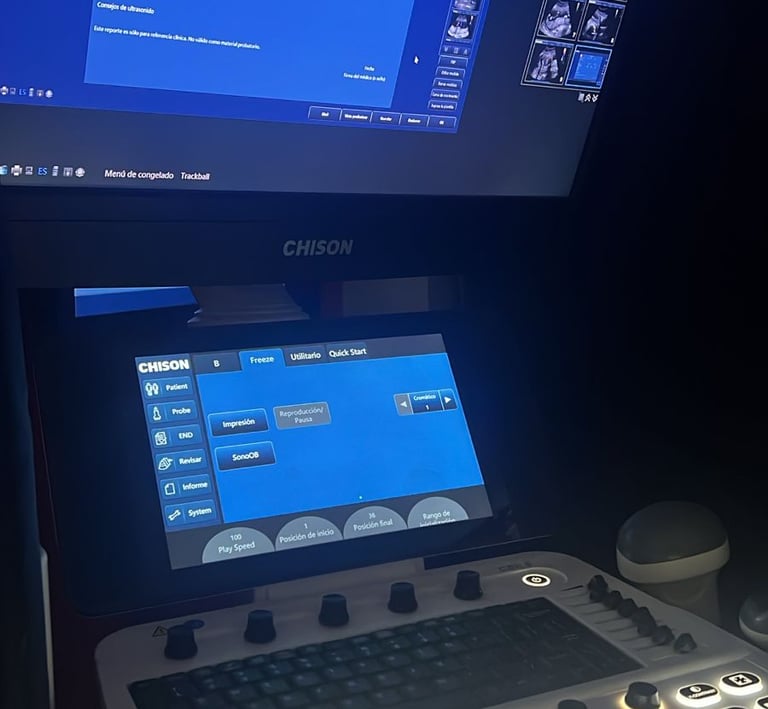

Ultrasonido Prenatal

Estudio prenatal seguro y sin dolor para controlar la salud y el desarrollo de tu bebé.

Contamos con equipos de vanguardia para un mejor resultado.